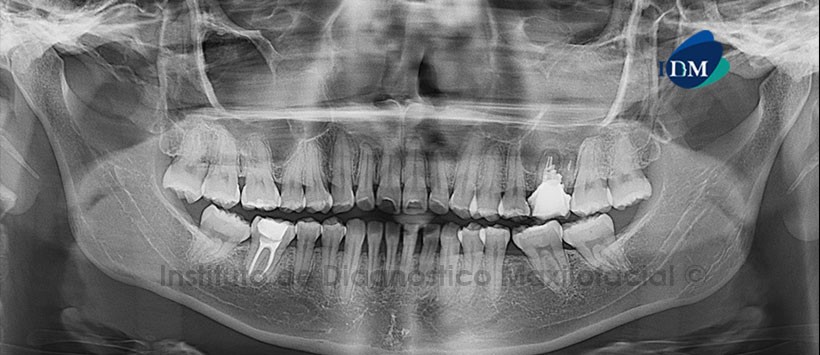

Paciente femenina de 20 años de edad que es referida al Instituto de Diagnóstico Maxilofacial, por manifestar dolor a nivel de la pieza 26. En la radiografía panorámica se observa el aplanamiento del contorno de los cóndilos mandibulares, la neumatización alveolar de los senos maxilares, ausencias de las terceras molares inferiores, múltiples restauraciones coronarias y lesiones de caries en las piezas 25 y 37. Así mismo, se evidencia la opacificación del seno maxilar del lado izquierdo en aparente asociación con el proceso osteolítico a nivel de la pieza 26 (Fig. 1).